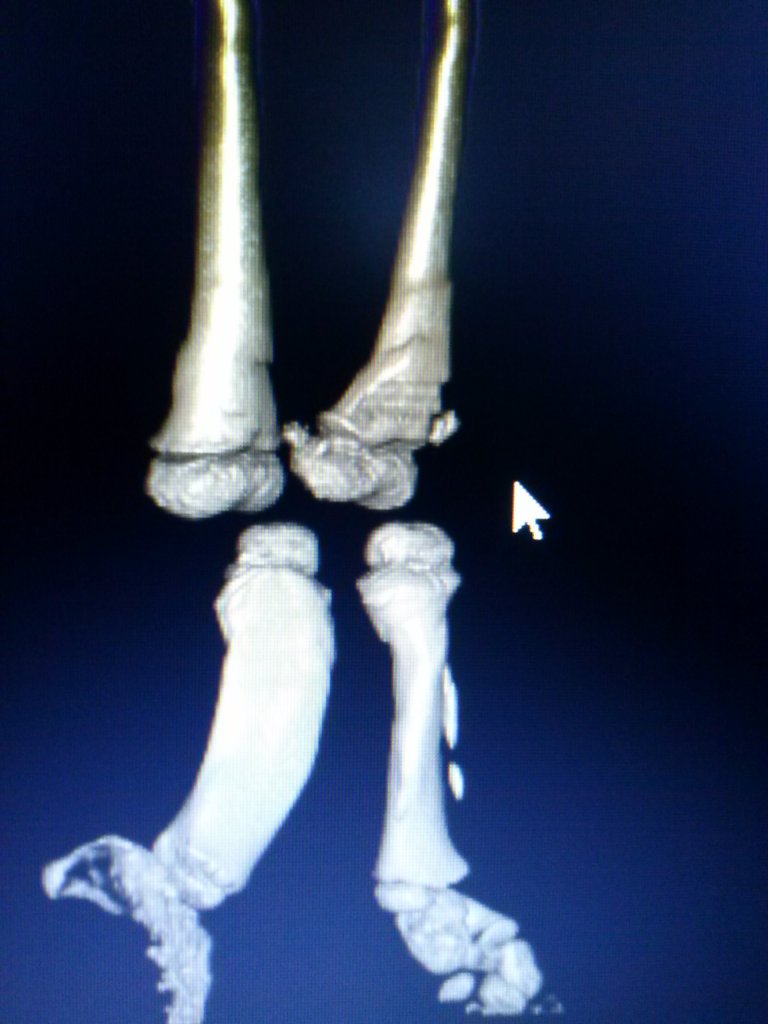

Lina namuncura

raquitismo congenito

Pese a tomar la medicacion indicada desde pequeña, mis huesos se deformaron tanto por mi raquitismo que me impedian caminar y solo podia trasladarme en silla de ruedas.tras varias consultas en diferentes centros del pais donde me decian que no podia hacerse nada llegue a Cotram.

fue en ese momento y tras una consulta de mas de una hora donde me explicaron paso a paso las cirugias necesarias para lograr lo que yo queria

luego de un año de tratamientos y cirugías logre enderezar todos mis huesos